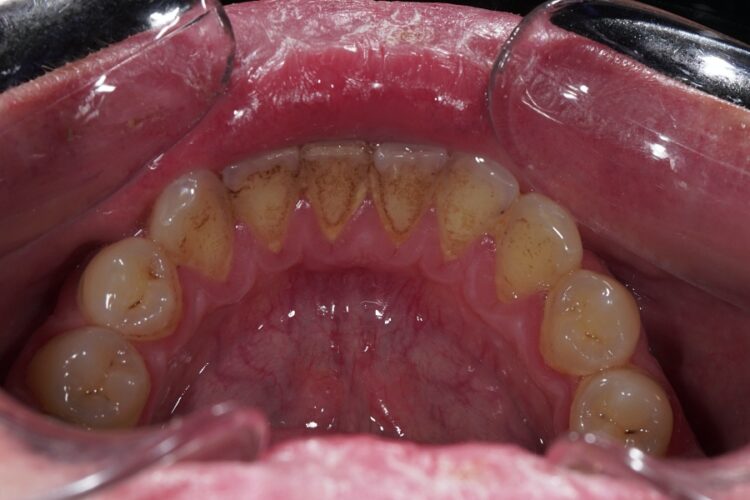

Professional oral hygiene is a complex of measures aimed at removing hard and soft dental plaque.

Professional teeth cleaning allows for the removal of dental calculus and dense plaque from the surface of the teeth and roots. Dental calculus is an irritating factor for the gum tissues that provokes acute and chronic inflammation of the gingival margin - gingivitis. One of the stages of teeth cleaning is polishing their surface as well as the surface of exposed roots. A smooth surface is less prone to the accumulation of dental calculus and plaque.

This involves removing supra and subgingival dental deposits (calculus) using ultrasonic technology. This procedure allows for a delicate cleaning of the teeth from calculus and stimulates blood circulation in the gums.

Features of professional teeth cleaning

Ultrasonic teeth cleaning is performed using a device that generates waves with a frequency of 40,000 oscillations per second. To cool the enamel and quickly remove fragments of hard plaque, a fine-dispersed water mixture is fed through a special nozzle of the device. Ultrasound is used to break up subgingival calculus and restore blood circulation in the gum tissue.